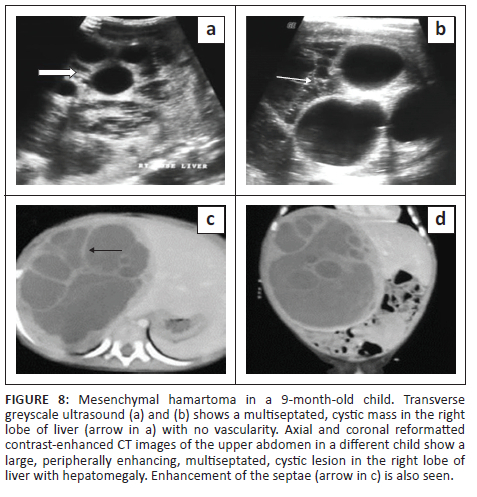

On postnatal ultrasound in infants and young children, the mass is predominantly cystic or can have a mixed, cystic-solid appearance depending upon the predominant component (mesenchymal and stromal). Rarely, it can present as a purely solid lesion. The cystic component of the tumour can be purely anechoic with echogenic septations (Figure 8a-b) or can show internal debris or fluid-debris levels depending on the content (Figure 9a-b). Due to the lack of a tumour capsule, the tumour can grow to a very large size.4 Loculated fluid adjacent to the lesion in the subcapsular or perihepatic location suggests rupture (Figure 10a-b). Colour Doppler interrogation shows minimal vascularity. Ultrasound-guided intraoperative aspiration of fluid from the cystic components of the tumour to reduce its volume can facilitate surgical resection.15

Imaging with NCCT may show a multiseptated cystic or solid-cystic lesion. The cystic component shows fluid attenuation. Septations and solid components show enhancement on post-contrast studies (Figure 8c-d).5